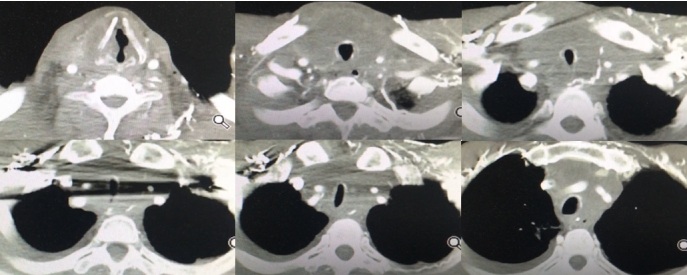

病例1(本院病例):中年男性,食道癌术后、放疗后复发。呼吸困难进行性加、吞咽困难3个月,拟行“气管支架置入术”收入院。查体:双肺呼吸音粗,可闻及喉鸣音。胸部CT提示颈部、纵隔占位,气管中段重度狭窄。

图片